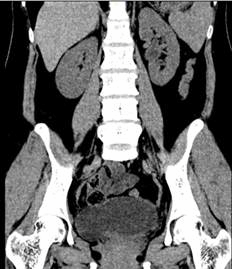

图三、四 术后3月泌尿系三维CT

在麻醉科和手术室的密切配合下,王春阳教授团队历时4小时,成功用6cm膀胱肌瓣替代了损伤的输尿管、留置输尿管支架完成手术。术中出血量仅20mL,术后连续观察三天没有再发生漏尿情况,患者顺利出院,出院3个月后引流管顺利拔除,仍无漏尿再发,治疗效果受到患者及家属高度认可。